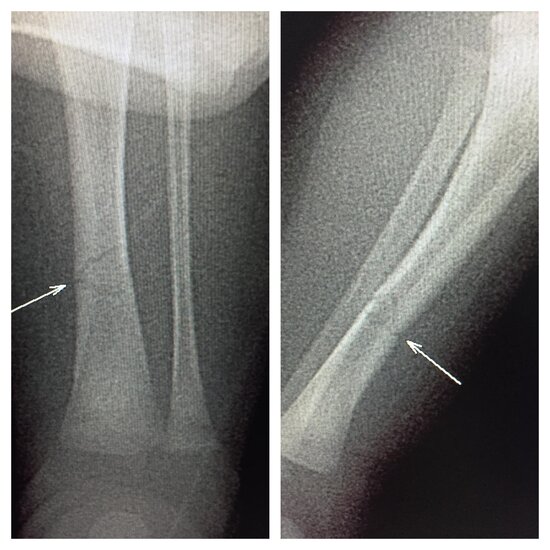

Bakıda 18 günlük körpənin qolu sındırıldı - FOTO

Bakıda 18 günlük körpənin qolu sınıb.

Məlumata əsasən, uşağın qolu 5 yaşlı bacısı tərəfindən ehtiyatsızlıqdan sındırılıb. Belə ki, o bilmədən əlindəki telefonu körpənin qoluna vurub və nəticədə uşağın qolu sınıb.

Dərhal körpə valideynləri tərəfindən özəl xəstəxanalardan birinə aparılıb. Müayinəsi davam etdirilir.